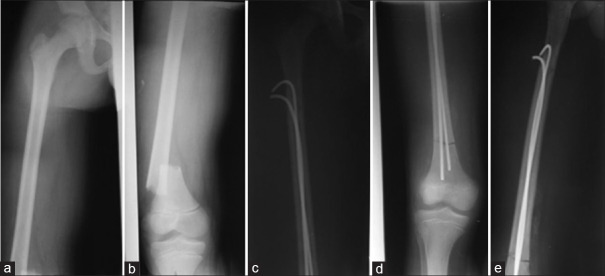

Results: Sixty-two patients underwent ESIN, of whom 44 patients (70.96%) were for femur fractures, nine patients (14.52%) for tibia and fibula fractures and nine patients (14.52%) for humerus fractures. The majority of the patients treated with ESIN were children older than 6 years. Nine patients (14.51%) and 13 patients (20.98%) underwent ESIN following polytrauma and multiple fractures, respectively. Seven patients (11.29%) were operated on through-closed ESIN method. The unavailability of image intensifier (38.71%) and the presence of bone callus (40.32%) were the major reasons for using the open ESIN method. Thirty-three patients (53.23%) had minor or major complications. The majority of patients had satisfactory therapeutic outcomes.

Conclusion: ESIN gives good results, even when the fracture site is approached.